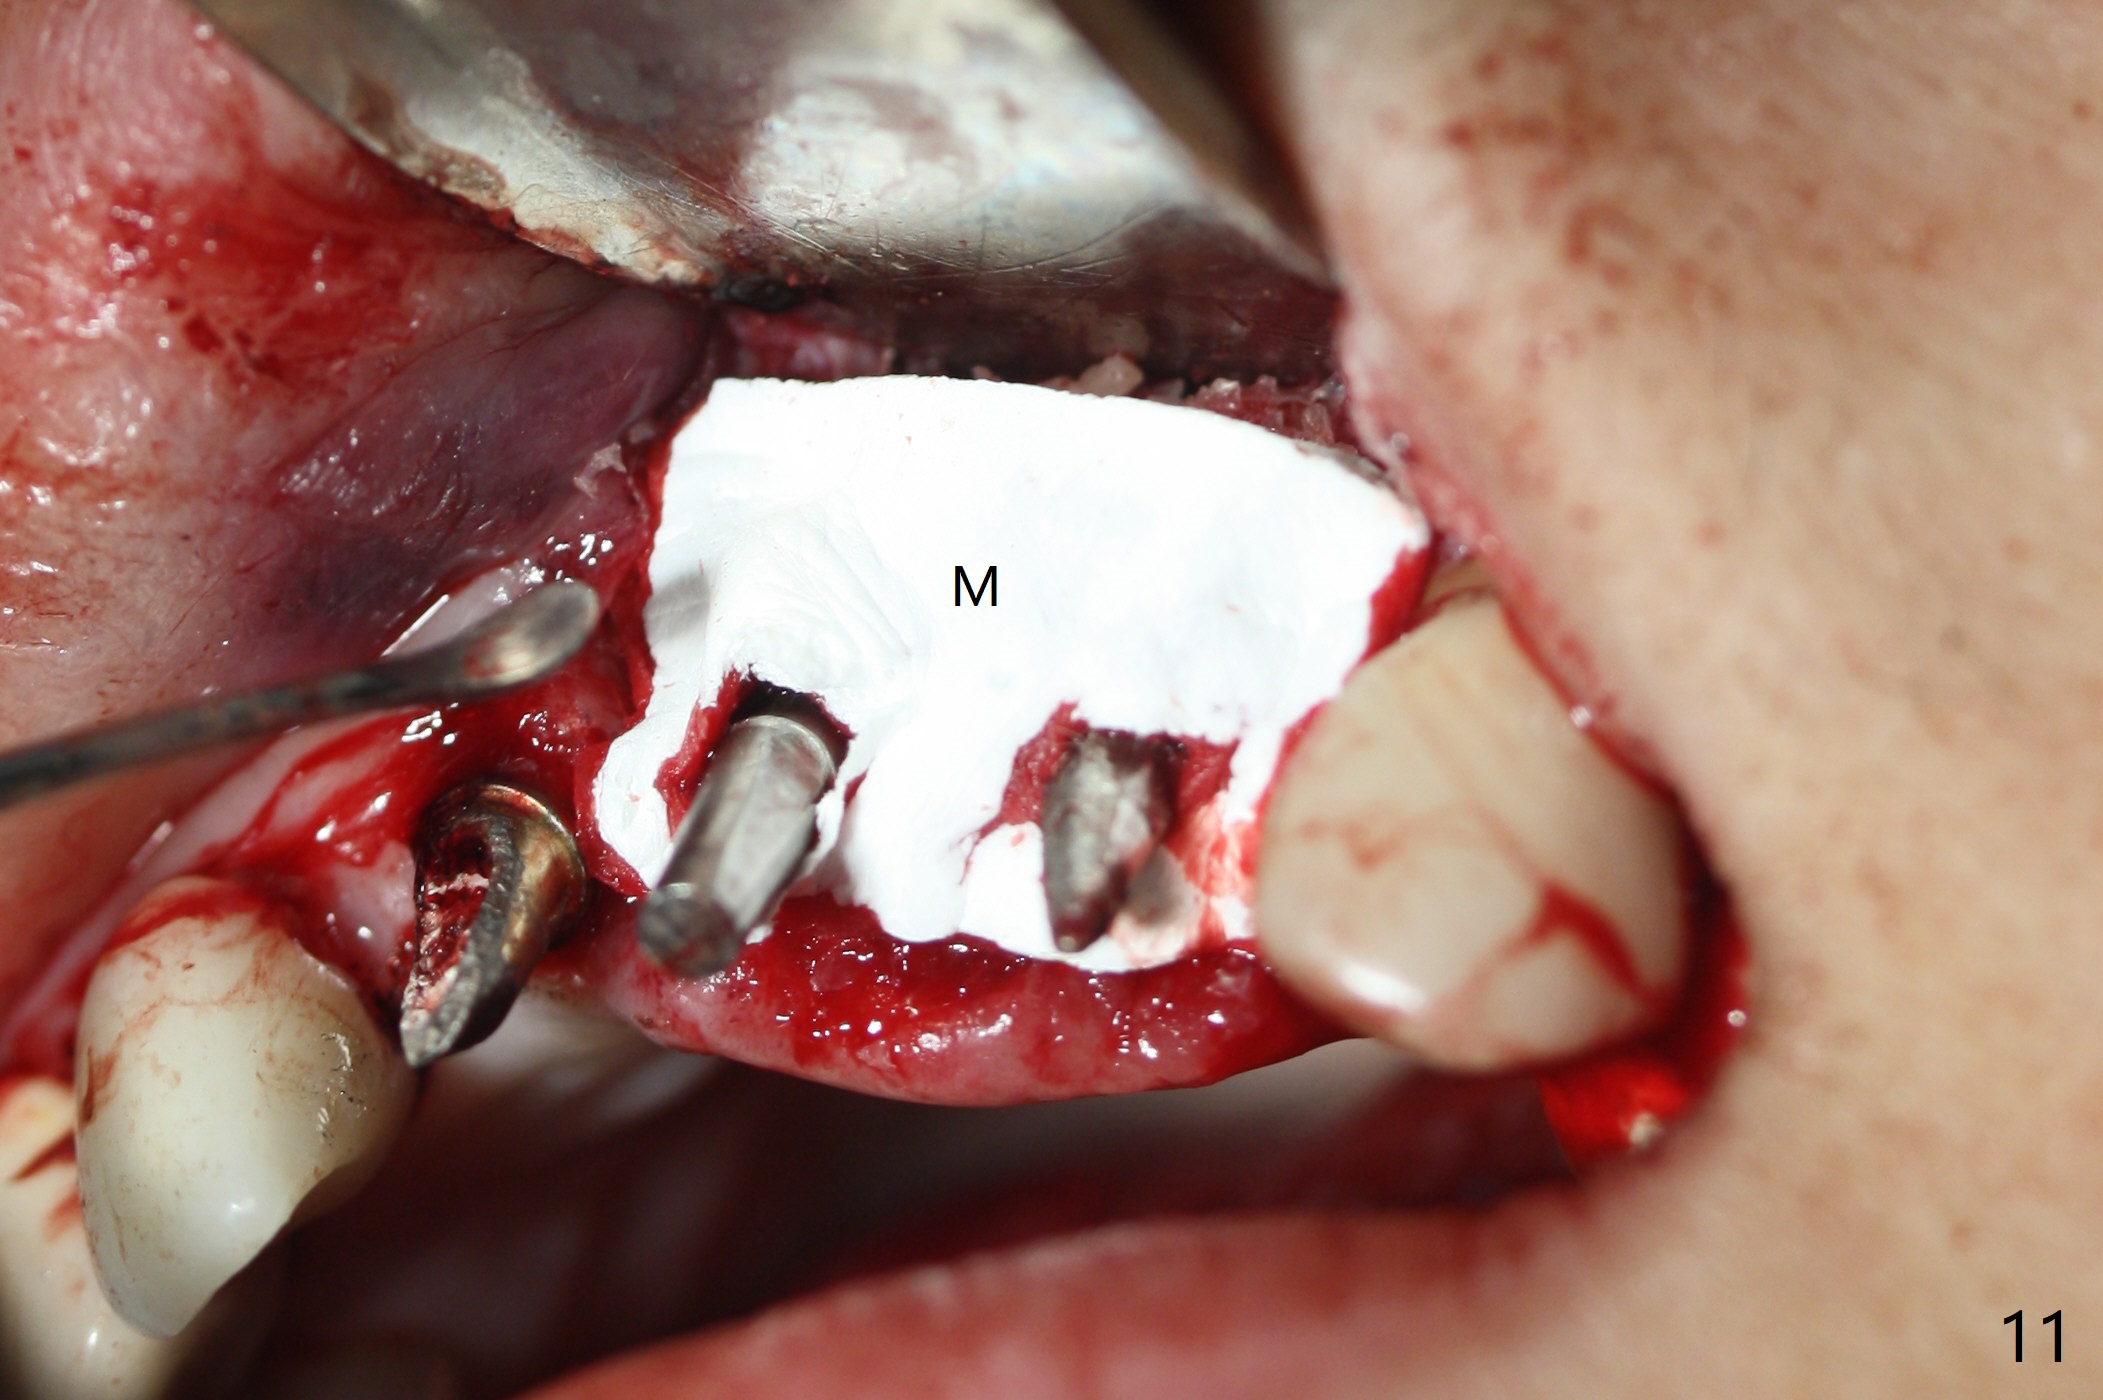

M

Incision shows exposure of microthreads at #9 and major threads at #10 due to buccal placement (Fig.1). There is bone palatal to the implant at #10 (Fig.2 P), to which a new implant will move. After implant removal, a narrower 1-piece implant (2.5x14(4) mm) is placed palatally at #10 (Fig.3,4) in combination of guide and free hand. At the site of #9 after implant removal, the guide is not used; a 3x17 mm angled 1-piece implant is placed with bad trajectory (Fig.5,6). After re-adjustment (Fig.7), the implant is placed at the right orientation (Fig.8). It appears that the guide is helpful. Allograft is placed mainly buccally (Fig.9,10 *), followed by a piece of collagen membrane (Fig.11). After tension release, flaps are approximated (Fig.12). The buccal gingiva at #9 and 10 recede nearly 2 months postop (Fig.13). Less recession at #9 is associated with more inflammation (Fig.14). The margin of the provisional is adjusted for gingival margin down growth and easy self cleaning with Water Pik (Fig.15). One month later, the gingival inflammation reduces, while there is no obvious buccal collapse (Fig.16,17). Impression is taken after laser gingivectomy nearly 4 months postop (Fig.18). While the gingiva around the implant at #9 is inflamed (periimplantitis?), the gingival cuff at #10 is well formed 5.5 months postop immediately before cementation (Fig.19). The buccal concavity at #10 is minimal (Fig.20). The gingival inflammation at #9 will be hopefully resolved after cementation of the final restorations (Fig.21). There appears to be new bone formation around the coronal implant threads 5.5 months postop (immediately post cementation, Fig.22). The microthreads at #9 may be not covered by the bone, the reason for the gingival erythema. The redness at #10 is asymptomatic 5.5 months post cementation (Fig.23). 粘固后两年牙槽嵴骨质并没有再生(图二十四),说明第一术中植体必须植入骨下(基台部分要长,否则难于修复),第二牙槽嵴处不应该有压力,植入2.5毫米植体,最后钻头应该是2.5毫米,骨下1-3毫米(尝试项目)。